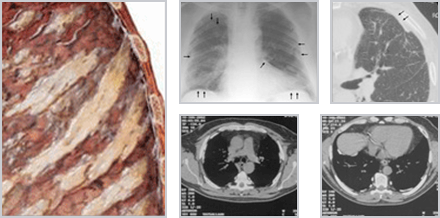

호흡곤란이 석면노출이 끝난 다음 여러 해 동안 서서히 진행 초기는 마른기침, 말기 화농성, 점액성 가래, 피로감, 체중감소 폐하엽이나 흉막인접 부위에서 진행 병이 진행되면 횡경막이 두꺼워 지고, 석면침착으로 폐 아래쪽에 진한 음영이 나타남 손가락 끝이 뭉툭해지는 지단거대증 발생(환자의 50% 이상) 누적노출량 25~100개/cc/year 석면노출량과 상관관계 5~45% 폐암으로 발전 |

| 폐암 | 1930 | 10~30년 | 폐에 암세포의 발생으로 인한 조직의 이상 |

호흡곤란, 피로감, 체중감소 누적노출량 25개/cc/year 석면노출량과 상관관계 1개/cc/10년 노출 폐암 발생 석면폐가 동반하면 석면에 의한 폐암 가능성 높음 폐암의 조직형태 : 편편상피암, 선암, 대세포암, 소세포 흡연자가 비흡연자보다 50배 이상 큼 |

| 악성 중피종 | 1960 | 20~40년 | 흉막 및 복막에 생기는 악성 종양 | 복부통증, 복부팽만, 가슴통증, 호흡곤란, 피로감, 식욕감퇴 급속진행 발병 후 1년 이내 사망 백석면 1개/cc/year에서 10만 명 노출군에서 5명 발생 석면노출의 지표 질환 석면 노출량과 관계가 희박하며 소량, 단기 노출에도 질병 을 일으킬 수 있음 |